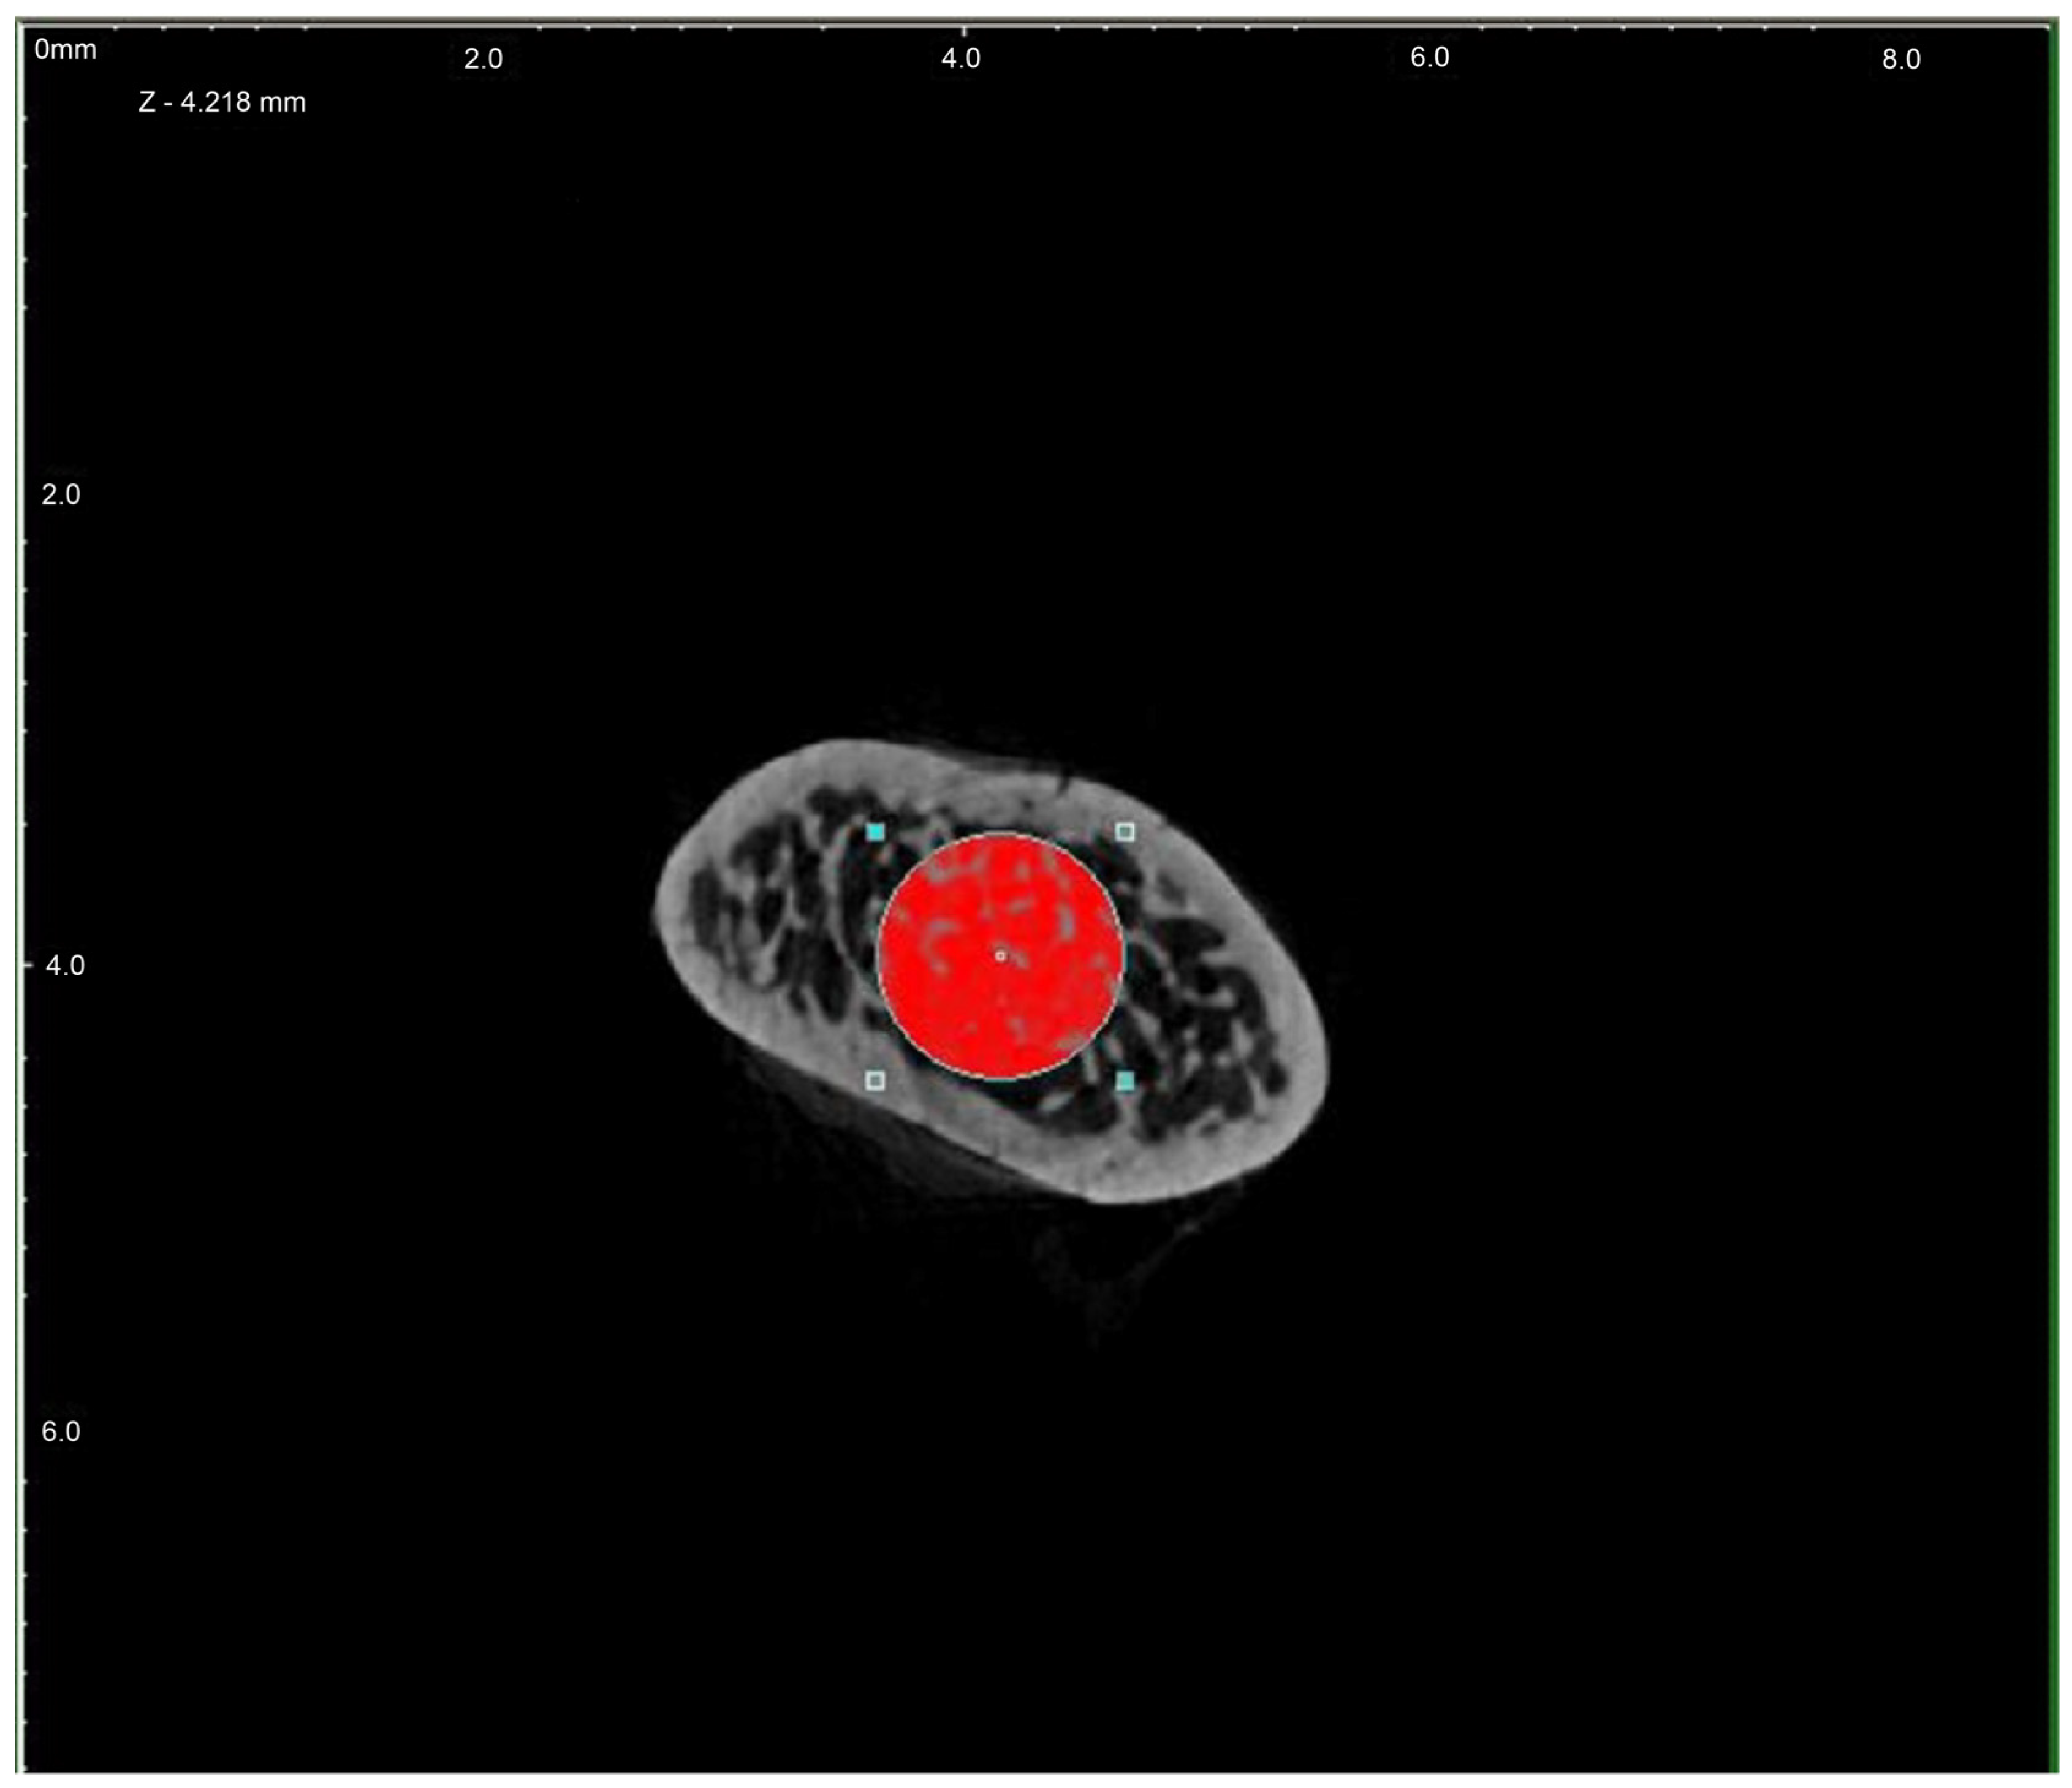

In order to evaluate the microarchitecture of bone tissue, the area of the distal metaphysis of the left femurs of all animals was subjected to microtomographic examination. After defrosting, the samples were placed on a centric stand in the center of the field of view of the microtomography chamber (Skyscan 1072, SkyScan, Antwerp, Belgium) and scanned (magnification 34×, Pixel 8.42, Rotation step 0.23, Exposure 1.9sec, and Gain 1). All of the samples were meticulously positioned so the mid-shaft of the bones was vertically straight and the orientation of the bones was consistent. Raw scans were reconstructed using the nRecon program (Skyscan, Belgium) and then thoroughly analyzed using the Ctan program (Skyscan, Belgium). An identical ROI (region of interest) was subjected to detailed morphometric evaluation. For the trabecular bone in all samples, a 100-slice cylinder was set in the central part of the distal epiphysis at a visual distance from the cortical bone, at the height of 85% of the bone length (Figure 1 and Figure 2). The analysis started at the most proximal end of the distal growth plate, which was visually identified in subsequent sections and taken as the reference point. In the ROI of each tested sample, the following microarchitectonic parameters were analyzed: percent of bone volume (BV/TV), trabecular thickness (Tb.Th), trabecular number (Tb.N), and trabecular separation (Tb.Sp). The surface of the cortical bone was assessed by subtracting the area whose outer border was the cortex’s inner circumference from the femur’s total surface at the level of the most proximal scan of the ROI from each group. Length measurements were measured from the left femur using a caliper. Representative micro-CT overview images are shown in Figure 3, Figure 4 and Figure 5.

Figure 2.

Region of interest (ROI) chosen for investigation—cross-section (red).